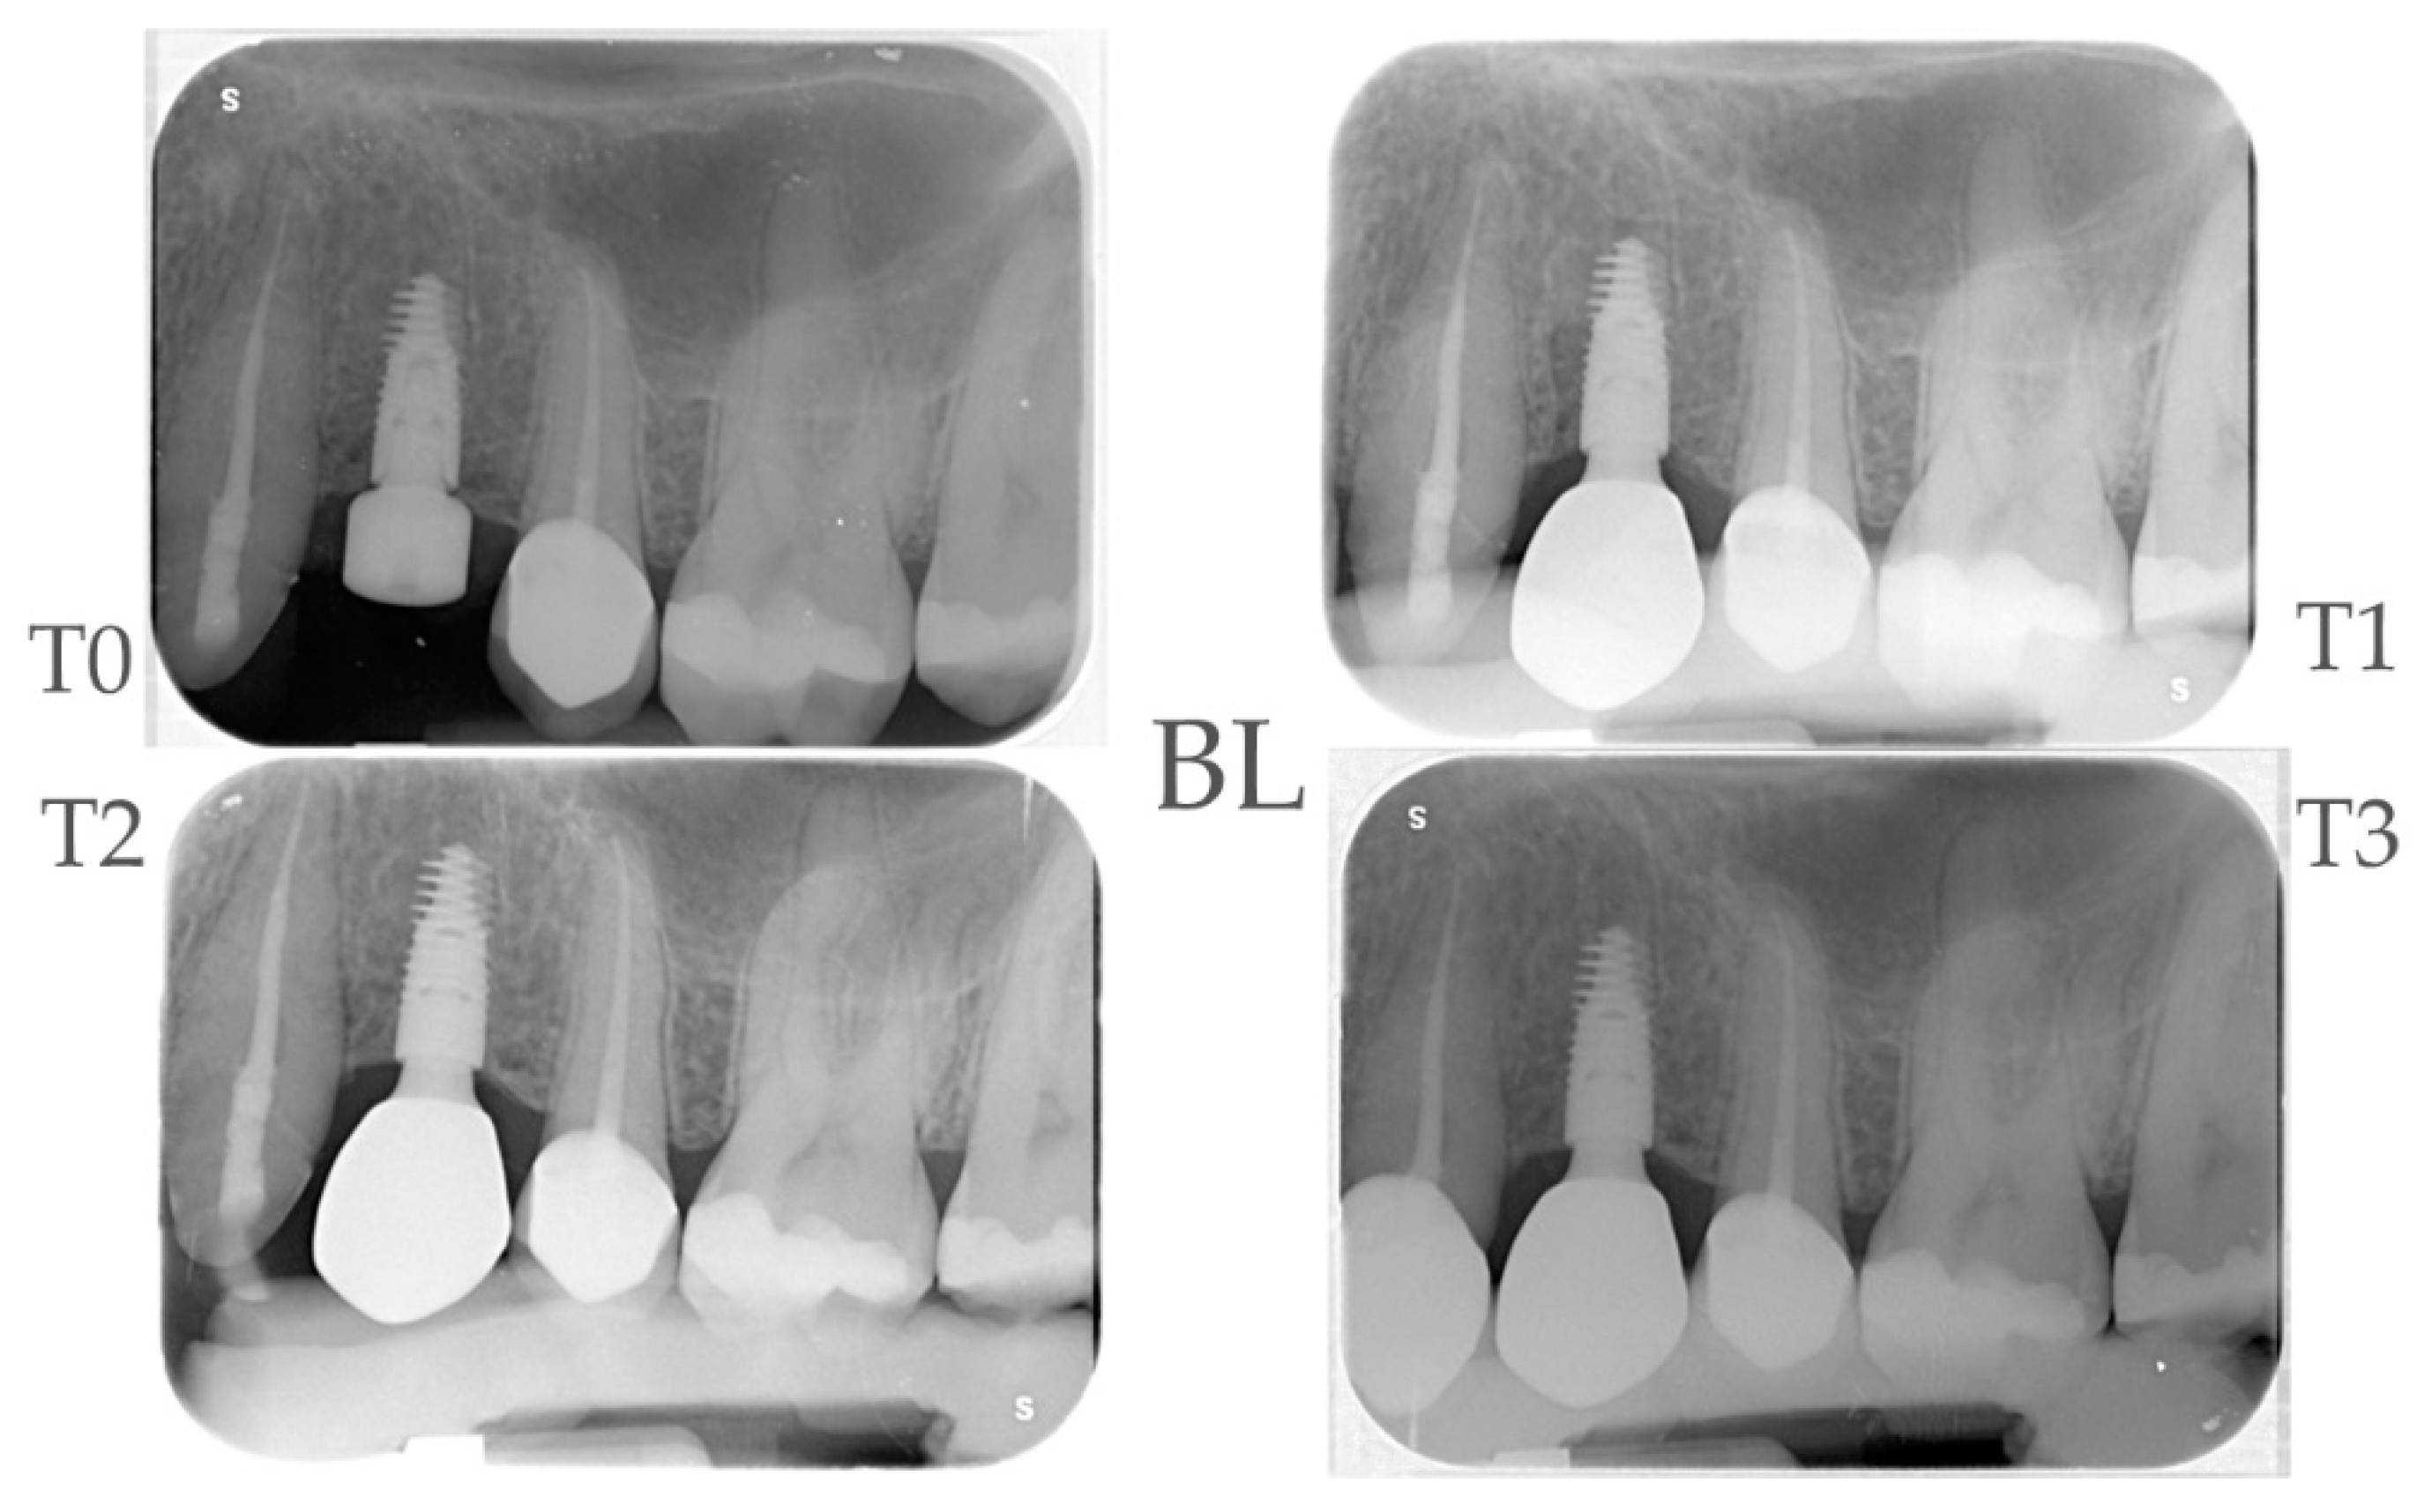

2.4. Radiographic Evaluations